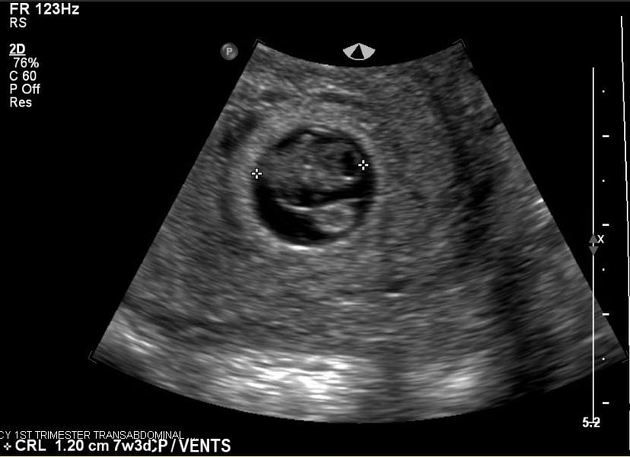

Маловодие в первом триместре беременности по УЗИ